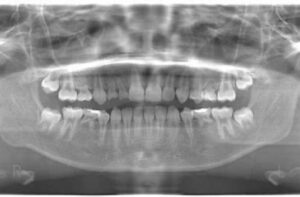

乳歯が抜けてしばらく経つのに永久歯が生えてこないとか、学校検診で指摘されて永久歯の数が足りない先天性欠如を知ることになって受診されることも少なくありません。先天性欠損は、遺伝的要因が主な原因とされていますが、環境的な要因や全身疾患、発生過程の異常も関係していると言われています。先天性欠如の約70〜80%は遺伝的背景があるとされています。家族にも歯の欠損があるケースが多く、常染色体優性遺伝が関与するともいわれます。特に上顎、下顎の第二小臼歯や上顎側切歯の先天欠如は、遺伝性が強い傾向があります。永久歯の先天欠如の頻度は日本人で約7%前後らしいです。

先天的に1~2歯の永久歯が欠損している子どもにおいては、乳歯が抜けてしまう時期、欠損の部位や数、周囲の歯の状態、咬合関係によって、顎の成長に次のような影響が出る可能性があります。